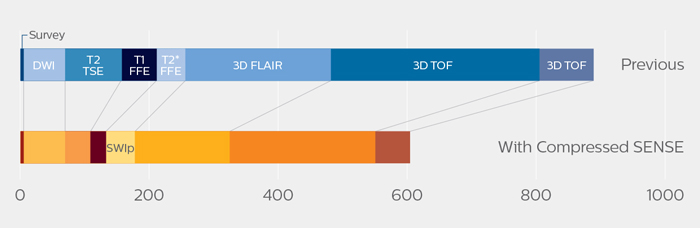

“We started scanning with a new set of ExamCards in which several sequences were replaced by sequences with Compressed SENSE,” says Dr. Koyasu. “We performed only a little further tailoring of ExamCards to meet our preferences. And as a result, we now can scan four brain exams per hour instead of only three before using Compressed SENSE.” The KNC team significantly reduced the scanning time of their most used ExamCards, see table and diagram.

Reduction of scanning time with Compressed SENSE

in ExamCards of KOYASU Neurosurgical Clinic

| KNC ExamCard | Total scan time before | Total scan time with Compressed SENSE | Change |

| Brain | 15:48 min. | 10:19 min. | -35% |

| Cervical spine | 13:11 min. | 9:52 min. | -25% |

| Lumbar spine | 11:41 min. | 8:17 min. | -34% |

Scanning time reduction in brain MRI with Compressed SENSE

With Compressed SENSE, the scan time for the routine brain examination at KNC was reduced from 15:48 to 10:19 minutes, which corresponds to 35% reduction.